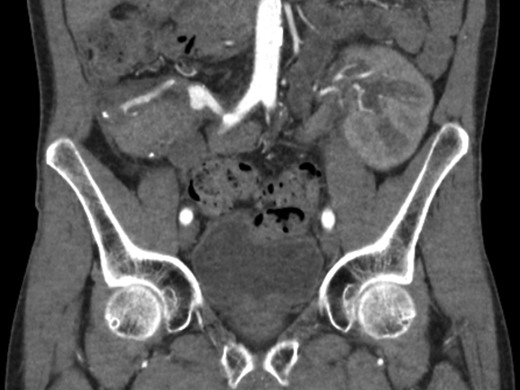

Eventually the patient recovered and could be discharged in good condition. An outpatient follow-up CT, however, showed an aneurysm of the pancreatic graft’s arterial reconstruction, most likely at the site of the anastomosis of the iliac Y graft with the splenic artery (Fig. 2), with the peripancreatic abscess as the most likely cause. Because of its size and growth, consent was given for removal of the pancreas, with subsequent pancreatic islet isolation and transplantation to retain beta cell function.

Elective CT scan showing pseudoaneurysm of the vascular reconstruction, most likely at the site of the anastomosis between Y graft and splenic artery.